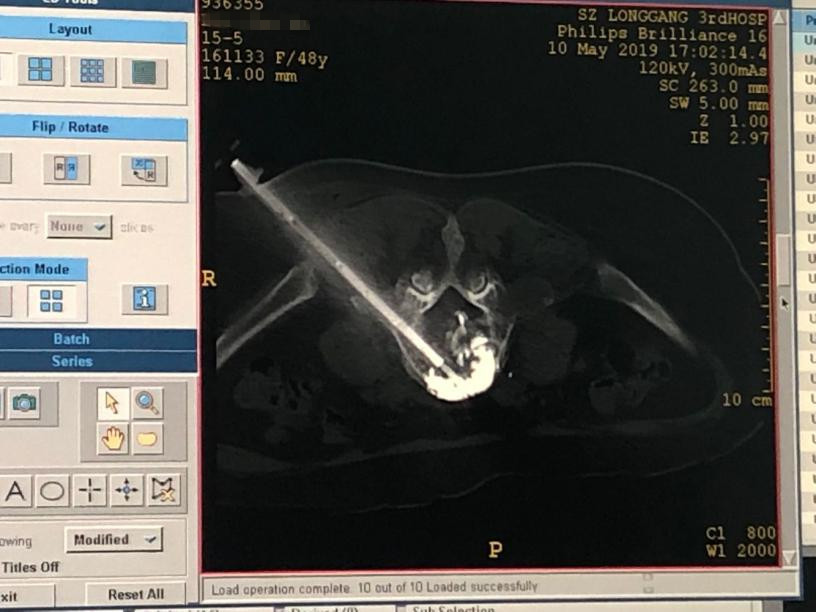

普外科(肿瘤微创介入诊疗中心)汤长江主任带领科室医师多次讨论病情,并与国内权威专家进行远程会诊,最终决定为邱女士和刘女士实施 CT 引导下椎体转移瘤经皮微波消融联合骨水泥成形术,该技术的最大特点是微创、局麻、出血少、手术时间短、手术后即可下床活动等优点,在微波杀灭肿瘤的同时,利用灭活瘤段进行骨水泥重建,保持了脊柱的稳定性,避免了过去传统开放手术带来的巨大创伤和痛苦。

5月10日上午,普外科(肿瘤微创介入诊疗中心)在外院专家指导下,手术麻醉科及放射科的共同努力下顺利完成两例椎体转移瘤经皮微波消融联合骨水泥成形术手术,历时平均50分钟。术后患者症状明显减轻,12小时后便可下地活动,从入院的扶墙走到自已独立行走,患者对该微创技术甚是满意,避免了过去需传统开放手术带来的巨大创伤及苦痛。